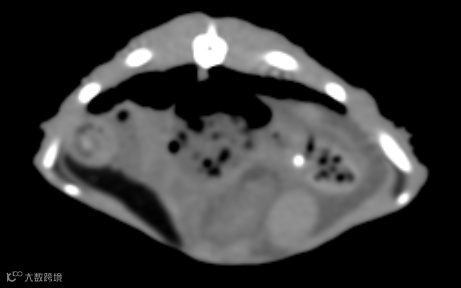

提升诊断精度:赛诺威盛动物CT集合了中国智慧和创新精神,采用先进的成像技术、智能的后处理应用和标准化的操作设计。可清晰捕捉动物的细微结构,为动物医疗提供精准、清晰的影像诊断,对珍稀物种研究具有突破性意义。